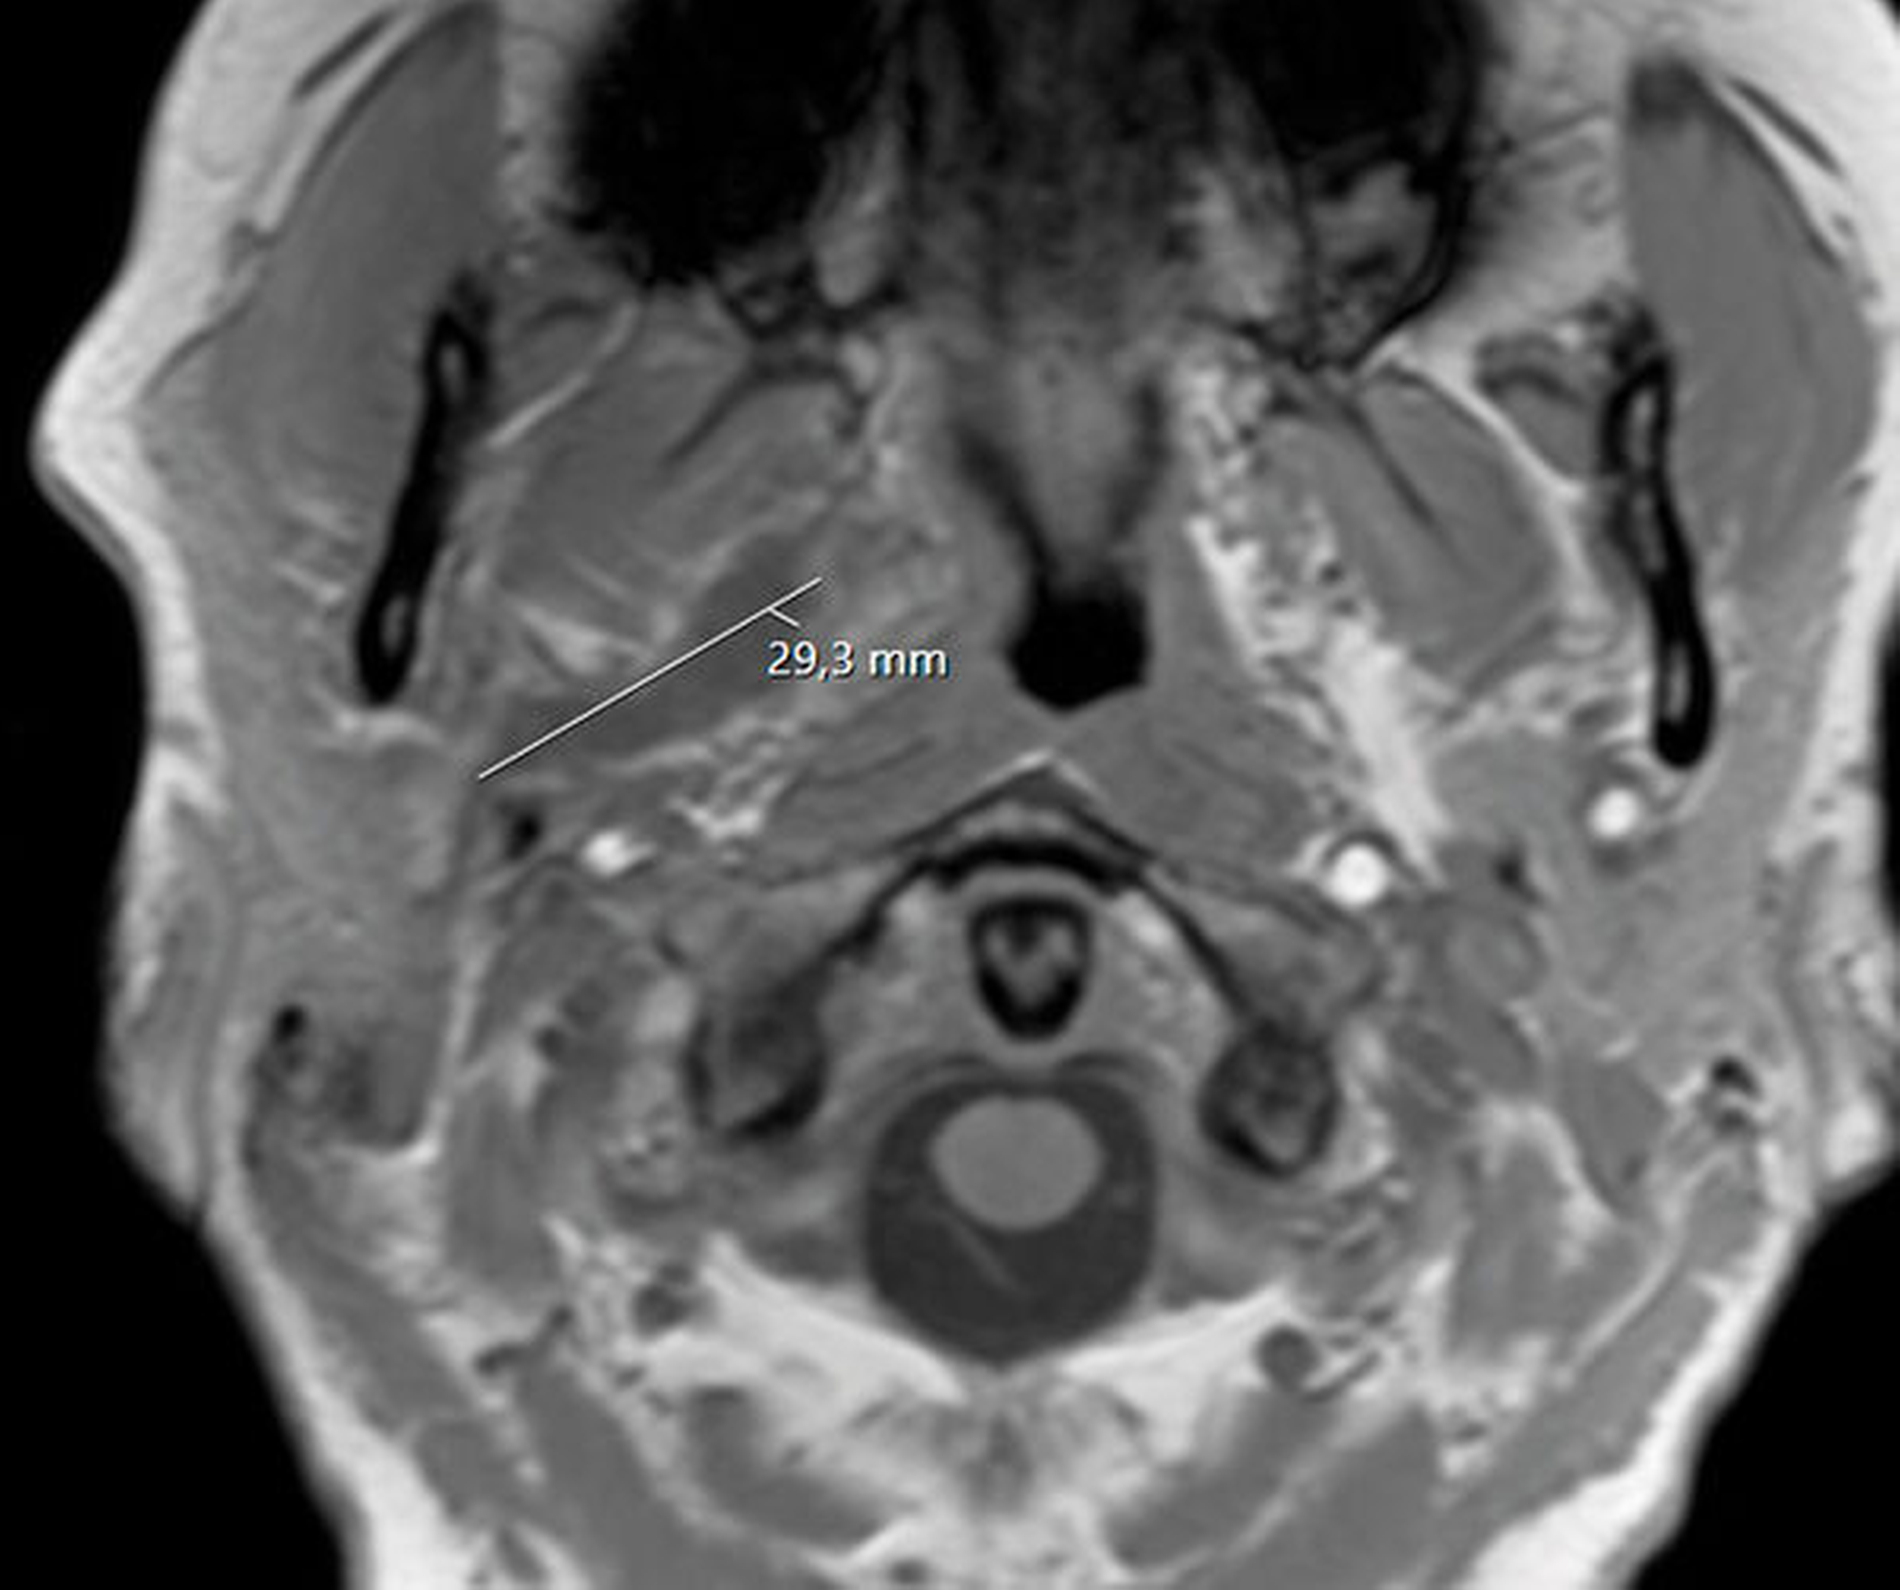

Unmittelbar nach der stationären Aufnahme wurde mit der intravenösen Antibiotikatherapie, Glukokortikoidgabe und antiphlogistischen Maßnahmen begonnen. Daraufhin zeigten sich die klinischen und die laborchemischen Entzündungsparameter rückläufig. Die Mundöffnung der Patientin war bereits am Folgetag mit einer Schneidekantendistanz von 40 mm deutlich verbessert. Zur Verlaufskontrolle und Beurteilbarkeit des Weichgewebes im Bereich der Mastikatorloge wurde am zweiten Tag nach stationärer Aufnahme eine Magnetresonanztomografie des Kopfes durchgeführt. Im Vergleich zur initialen Computertomografie der Halsweichteile zeigte sich eine zunehmende Resorption der liquiden ovalären Veränderungen in der rechten Mastikatorloge (Abbildungen 3 und 4). Zum Ausschluss einer otorhinolaryngologischen Pathologie wurde die Patientin konsiliarisch in der Hals-Nasen-Ohrenheilkunde der Universitätsmedizin Mainz vorgestellt. Die Kollegen fanden keine pathologischen Auffälligkeiten, so dass bei radiologisch rückläufigem Befund von einem Hämatom ausgegangen werden konnte. Am vierten Tag nach stationärer Aufnahme konnte die Patientin die Klinik mit nahezu normwertigen Laborparametern verlassen und in die ambulante Nachsorge entlassen werden.